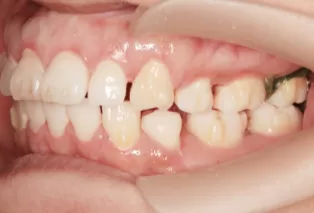

Before Treatment

Intraoral photos